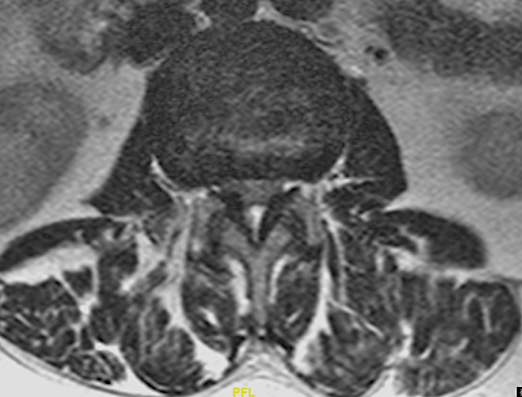

A continuación expongo imágenes de un caso prototipo donde podría estar indicado como alternativa a una descompresión y fusión larga.